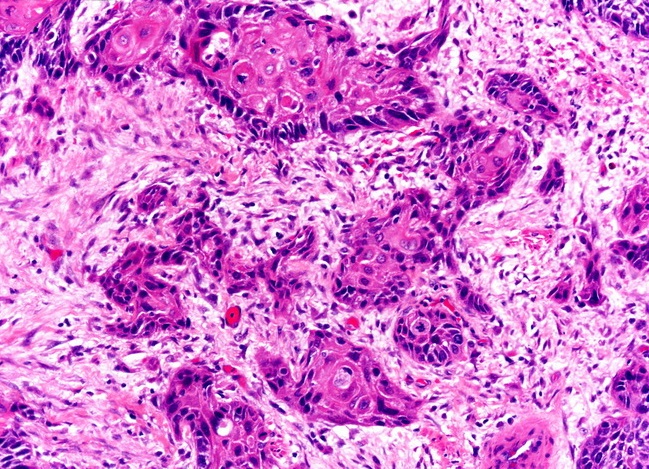

Высокодифференцированная аденокарцинома кишки